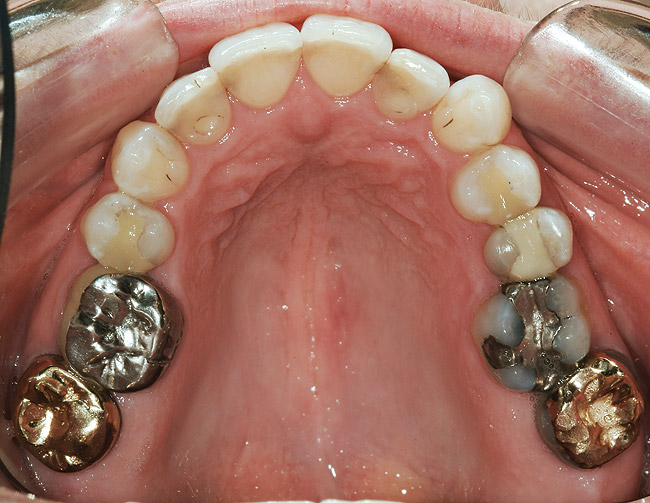

FUNCŢIONAL: La majoritatea dinţilor posteriori ai pacientei ce erau restauraţi cu coroane (fig. 6, 7) era importantă interpretarea minuţioasă a istoricului pacientei şi a rezultatelor evaluării ocluzale. Coroanele din aur de la nivelul 1.7. şi 1.4. prezentau orificii de uzură pe suprafeţele ocluzale, cu semne de minimă uzură pe celelalte coroane posterioare şi la dentiţia naturală. Era evidentă o uzură moderată pe coroana din aur a molarului 4.7.

Traumatismul ocluzal primar s-a observat la dinţii 1.5. şi 2.5. În intercuspidare maximă, s-a notat ocluzie deschisă la segmentele dentare frontale 1.3.-2.3. şi 3.3.-4.3. Dinţii 1.6. şi 4.6., precum şi 2.6. şi 3.6. erau în angrenaj invers (fig. 5, 8). Pacienta prezenta o ocluzie Angle Clasa I. Având în vedere rezultatele istoricului şi examinării s-a stabilit un diagnostic de disfuncţie ocluzală.